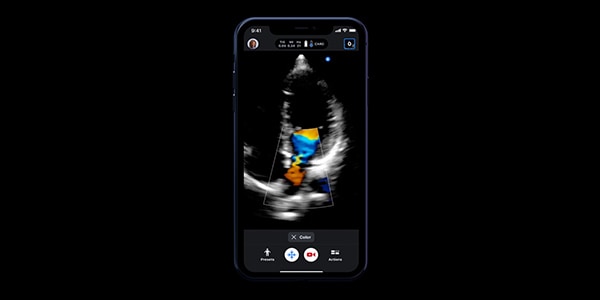

• Color Doppler: Color Doppler uses standard ultrasound methods to convert Doppler sounds into colors that are overlaid on the image of the blood vessel. These colors represent the qualitative parameters of haemodynamic behavior and direction of blood flow through the vessel.